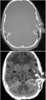

Depressed skull fracture

A skull fracture is a break in one or more of the eight bones that form the cranial portion of the skull, usually occurring as a result of blunt force trauma. If the force of the impact is excessive, the bone may fracture at or near the site of the impact and cause damage to the underlying structures within the skull such as the membranes, blood vessels, and brain. [Source: Wikipedia ]